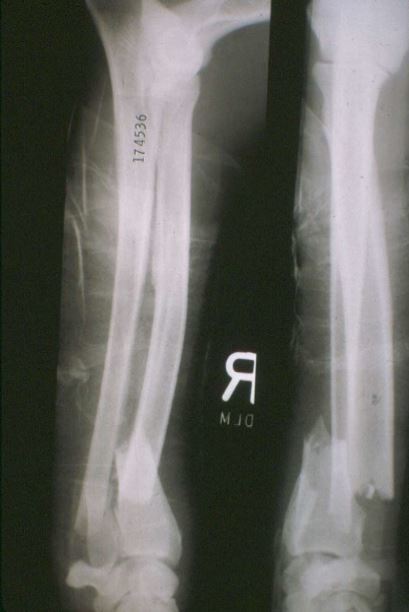

Q

4 month old mixed breed canine

Acute lameness RHL

Classify and assess fracture, and give repair options

Transverse fracture of the diaphysis of the tibia

Fx score= 8-10

Repair: ESF, Interlocking nail, External coaptation

Bone plate may be overkill (young patient)